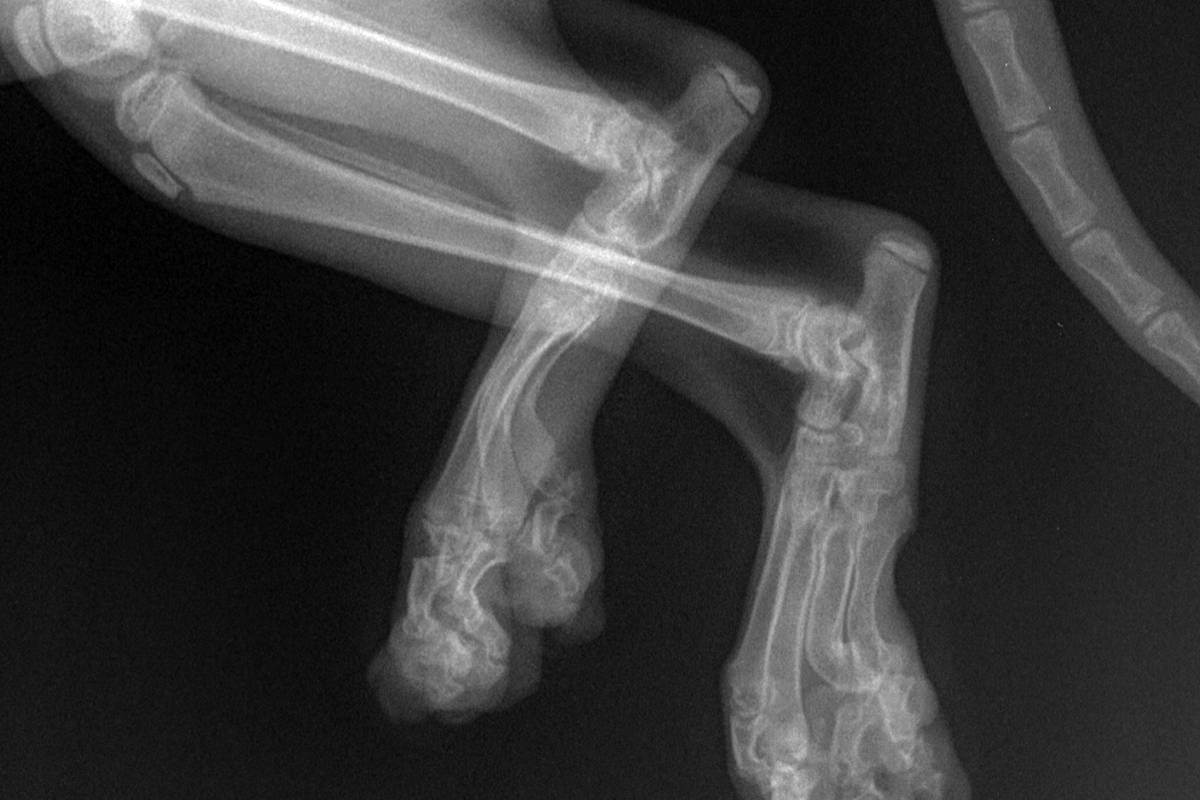

Остеохондродистрофия выражается в деформированном скелете, артритах, появившихся на данном фоне. Главным образом, сюда относятся искривленные передние и задние конечности, слишком толстый хвост, плохо развитая хрящевая ткань. Вылечить заболевание невозможно. На протяжении жизни кошке ведется поддерживающая терапия, но со временем наступает паралич.

Остеохондродистрофия на рентгене

Остеохондродистрофия у кошки